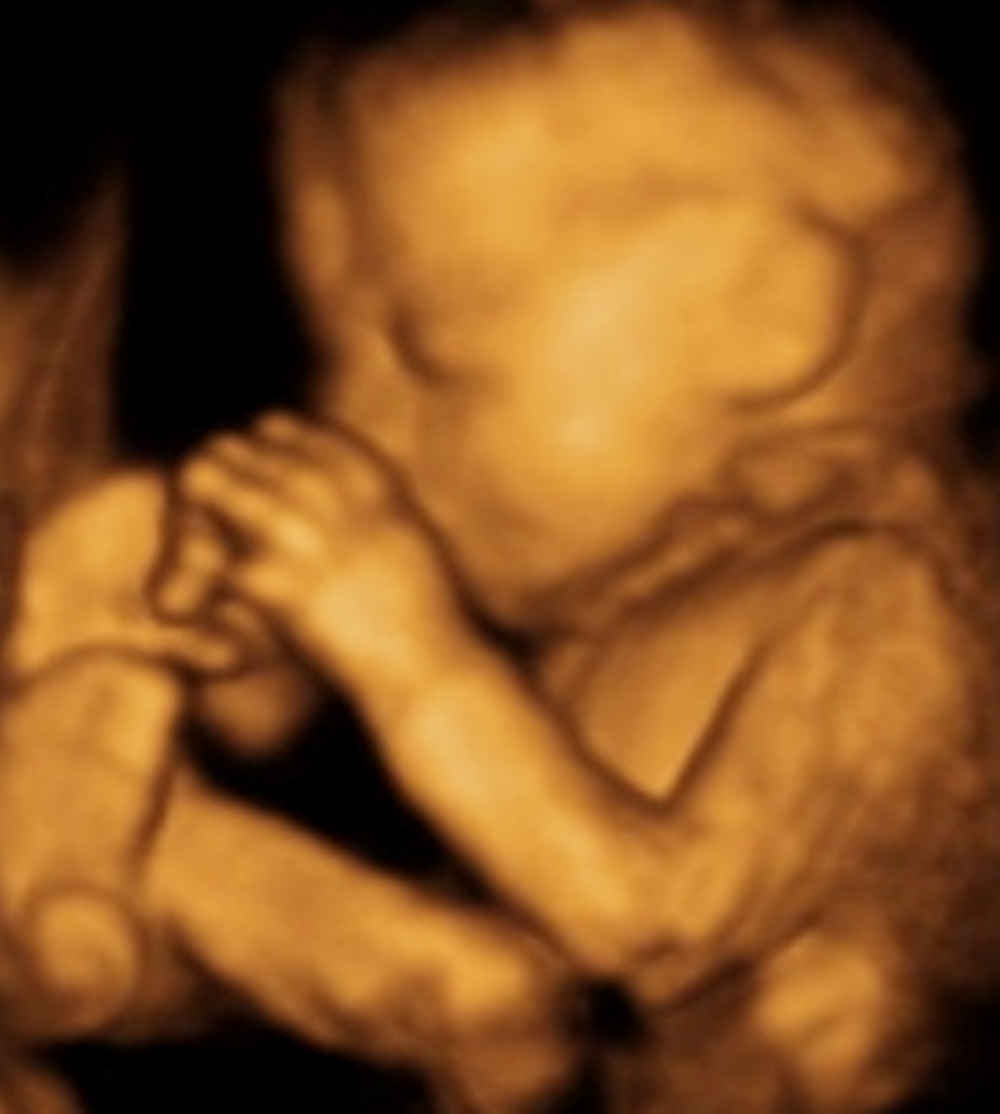

其中,最常见的情况就是在做四维检查的时候,宝宝总喜欢用手“捂着脸”,做出一副害羞的表情,很多妈妈就认为宝宝这么小就知道害羞了?

其实不然,宝宝喜欢“捂着脸”,是其他的几个原因。

为什么在做四维检查的时候,胎儿喜欢“捂着脸”?

1)空间太小

一般情况下,孕妈在孕期20-28周之间要去做四维彩超检查。这个阶段的胎儿,已经长到27厘米长,约重450g。

虽然体积还不算大,但实际上子宫内空间也并非可以让小宝宝“为所欲为”的。尤其是小腿和小手,更是不能伸直,小手一般都会放在脸的周围。

这个时候从彩超中看起来,胎宝宝的手就像是“捂着脸”一样,其实也是一种视觉错觉。